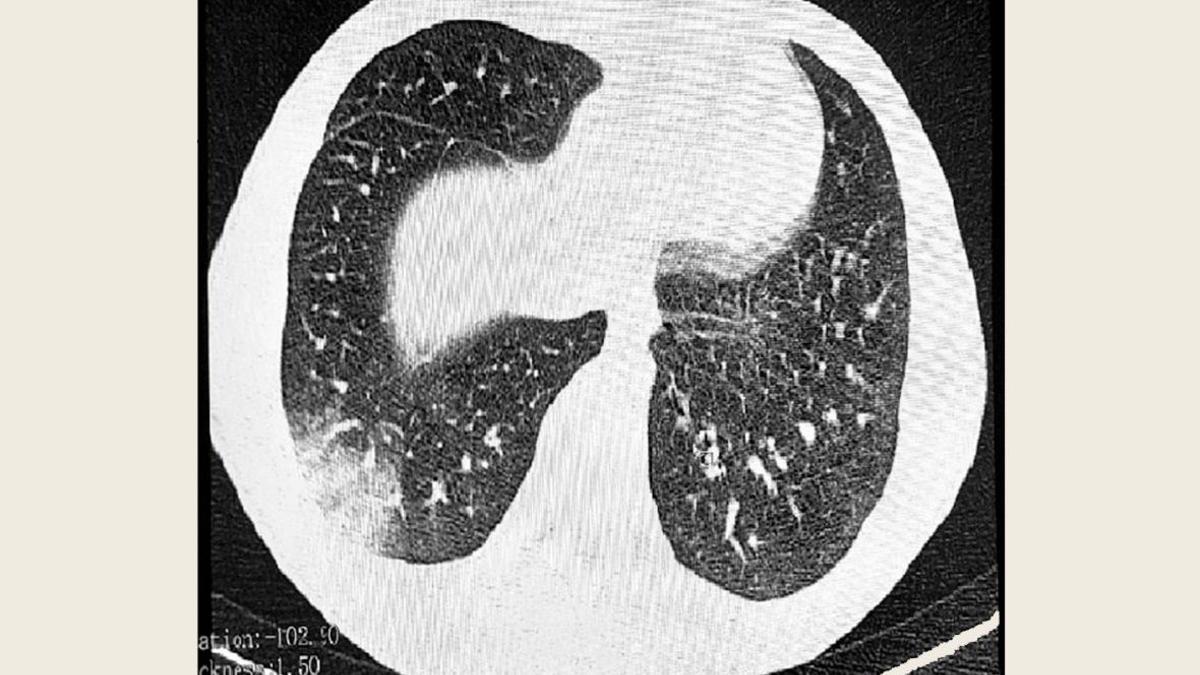

Сейчас диагностика EVALI является сложной, так как по симптоматике заболевание напоминает легочную инфекцию. Зачастую подросткам ставят диагноз «пневмония», по которой они получают безрезультатное антибактериальное лечение. Врач подчеркнула, что когда ребенок сталкивается с проблемами дыхания, необходимо обследование, включающее рентген легких, бронхоскопию, сдачу необходимых анализов.

Автор фото: управление Роспотребнадзора по Томской области